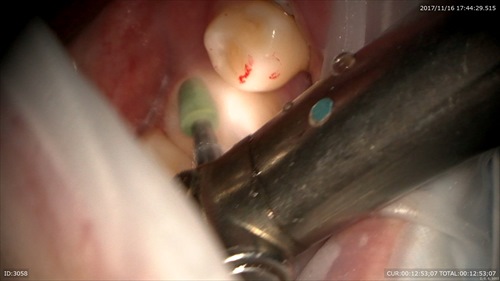

マイクロエンド

他院からの来院。汚染物がとれていませんでした。

マイクロエキスカで細かく丁寧に。

ストレートラインアクセス。根管口が見えます。

次回はMTAで根管充填します。治療回数は2回。